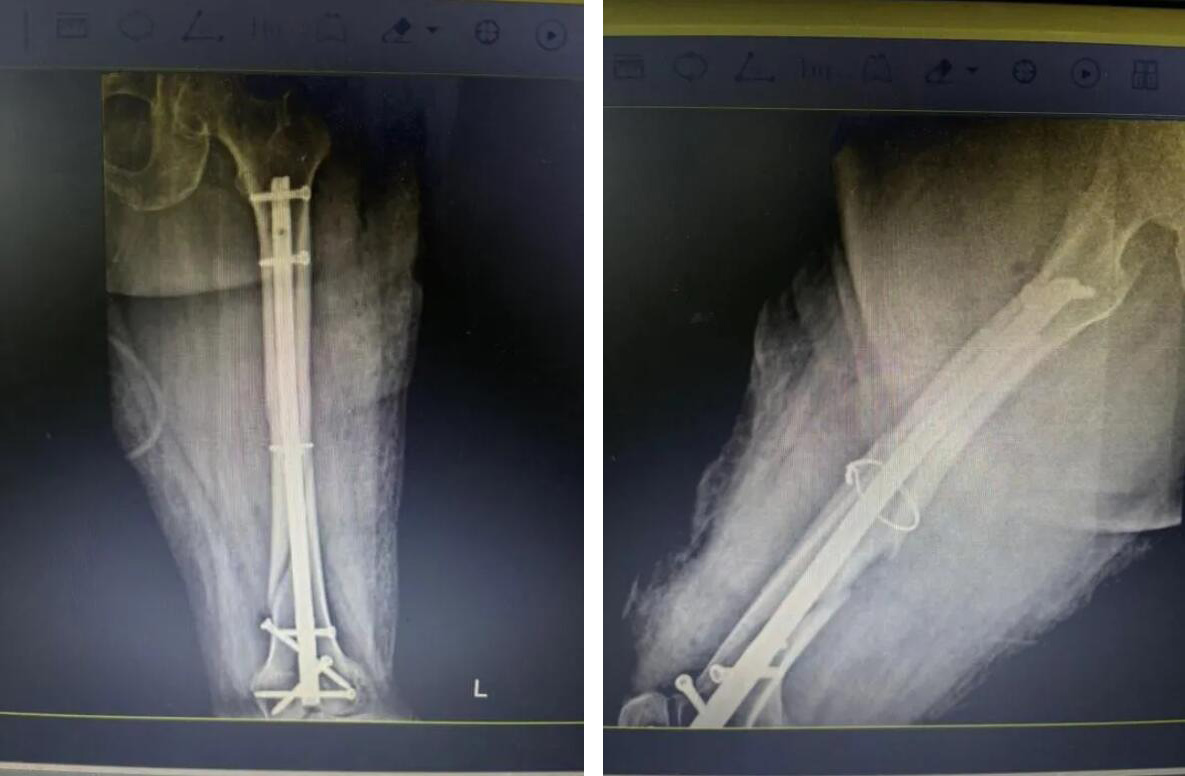

經(jīng)過充分準(zhǔn)備,醫(yī)療團(tuán)隊(duì)決定為俞奶奶實(shí)施 “閉合復(fù)位微創(chuàng)內(nèi)固定術(shù)”。

與傳統(tǒng)開放手術(shù)不同,醫(yī)生不在骨折處做長(zhǎng)切口,而是通過幾個(gè)僅1-2厘米的“鑰匙孔”小切口,在C型臂X光機(jī)的精準(zhǔn)導(dǎo)航下,將骨折斷端巧妙地對(duì)合復(fù)位,然后植入髓內(nèi)釘進(jìn)行堅(jiān)固固定。

手術(shù)歷時(shí)約一小時(shí),過程非常順利。術(shù)中出血量極少,最大程度減少了對(duì)患者生理機(jī)能的干擾。